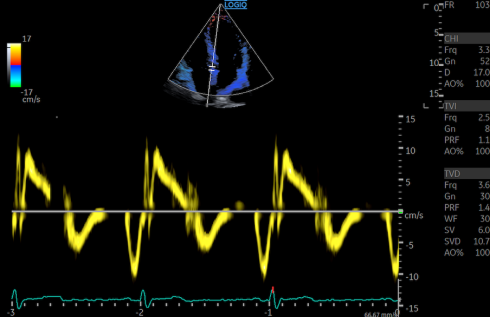

组织多普勒(TDI) * _! \3 x5 V7 h, `2 s3 \

组织多普勒(TDI)是一种典型的用于测量二尖瓣环和三尖瓣环处移动心肌的多普勒频率变化的技术。彩色多普勒(CDI)和PW模式下都可使用TDI 。DTI可在非常高的振幅下(>40 dB)检测非常低的速度(<20 cm/s) 。它的滤波器设置与标准PW对血流的设置有很大的区别。为使此多普勒模型最优化,推荐使用系统预设条件。DTI预设拥有比PW更大的取样容量,其速度标尺设置低于25 cm/s,有特定的滤波器、功率以及扫描速度设置。速度和时间间隔测量应在扫描速度为100 mm/s的情况下进行。